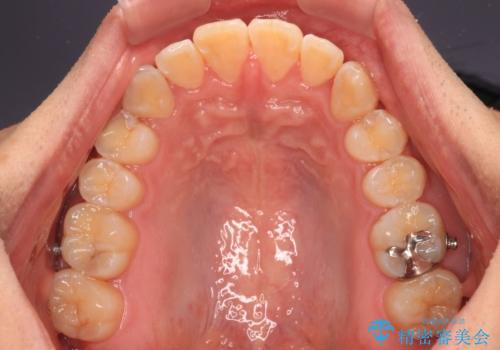

オープンバイトをインビザラインで矯正治療

- 前歯の開咬を気にして来院された患者様です。

開咬の治療は、前歯を閉じるように動かすとともに、上下臼歯を圧下(骨内にめり込ませる)させることで進めて行きます。

インビザラインは臼歯の圧下を効果的に行えるため、インビザラインを用いて矯正治療を行うこととしました。